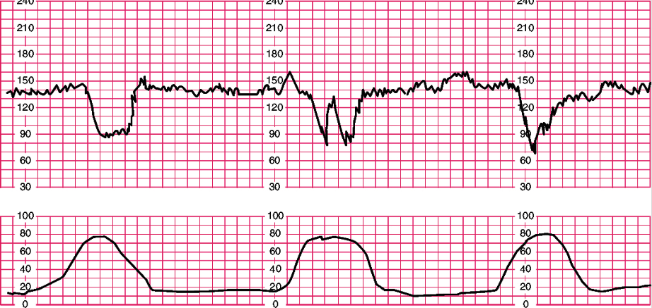

What is this? Explain why these occur. What are the nursing interventions?

Variable decelerations

This occurs because the cord is compressed.

Nursing interventions are to reposition the mother, amnioinfusion to flush fluids up to help float cord, give IVF, turn oxytocin off, and notify provider.

Late decelerations

They occurs because there is placental insufficiency.

Nursing interventions are to turn oxytocin off, position change, IVFs, sterile vaginal exam, notify provider, consider oxygen, and prepare women for potential C/S delivery.